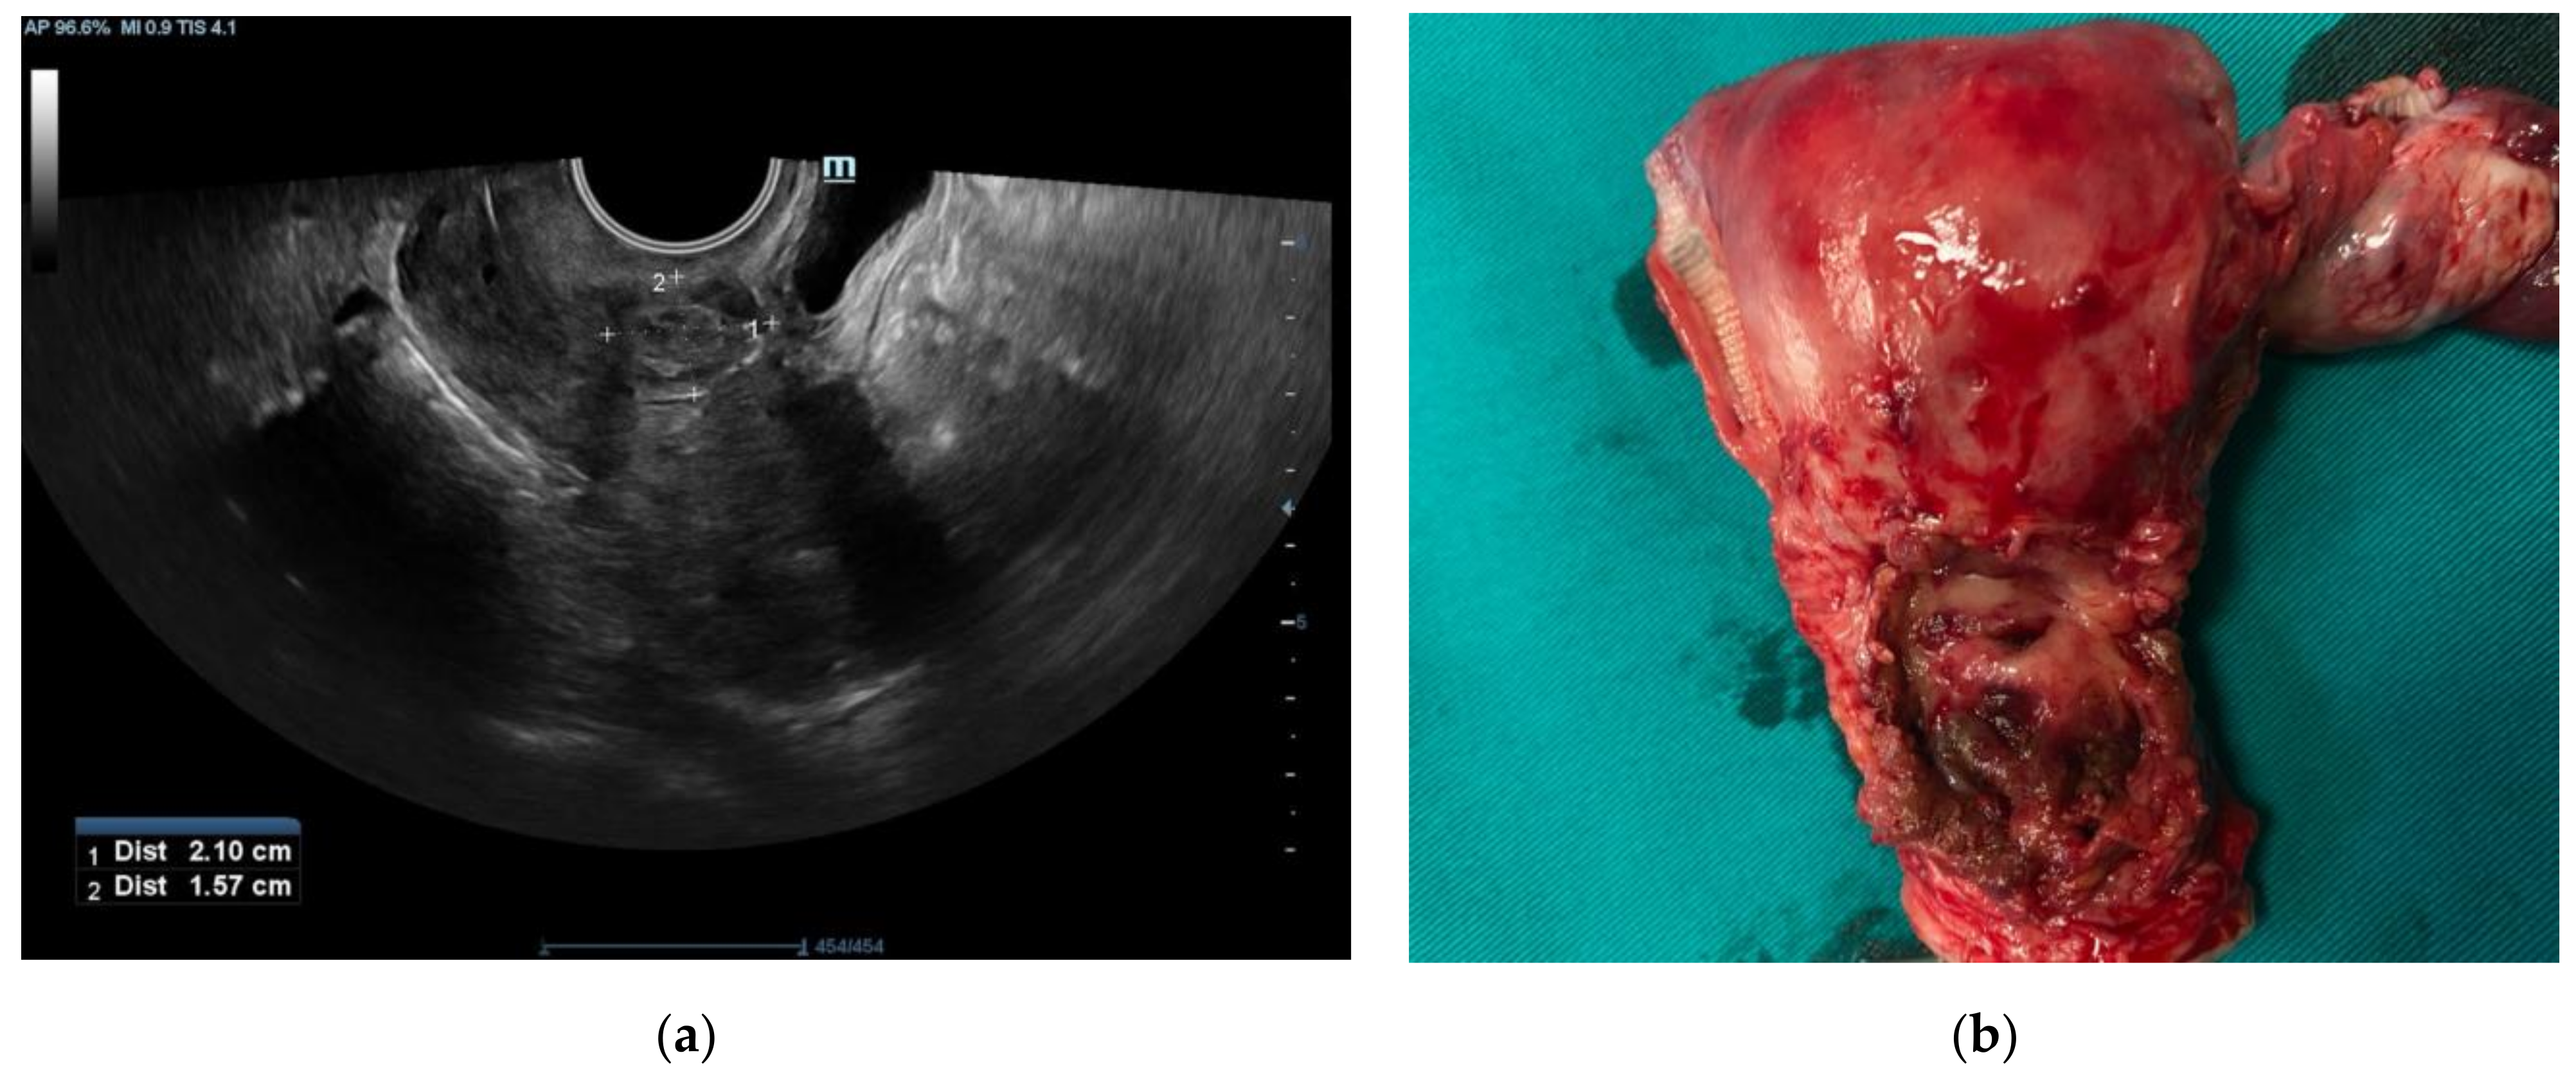

2. Case Report